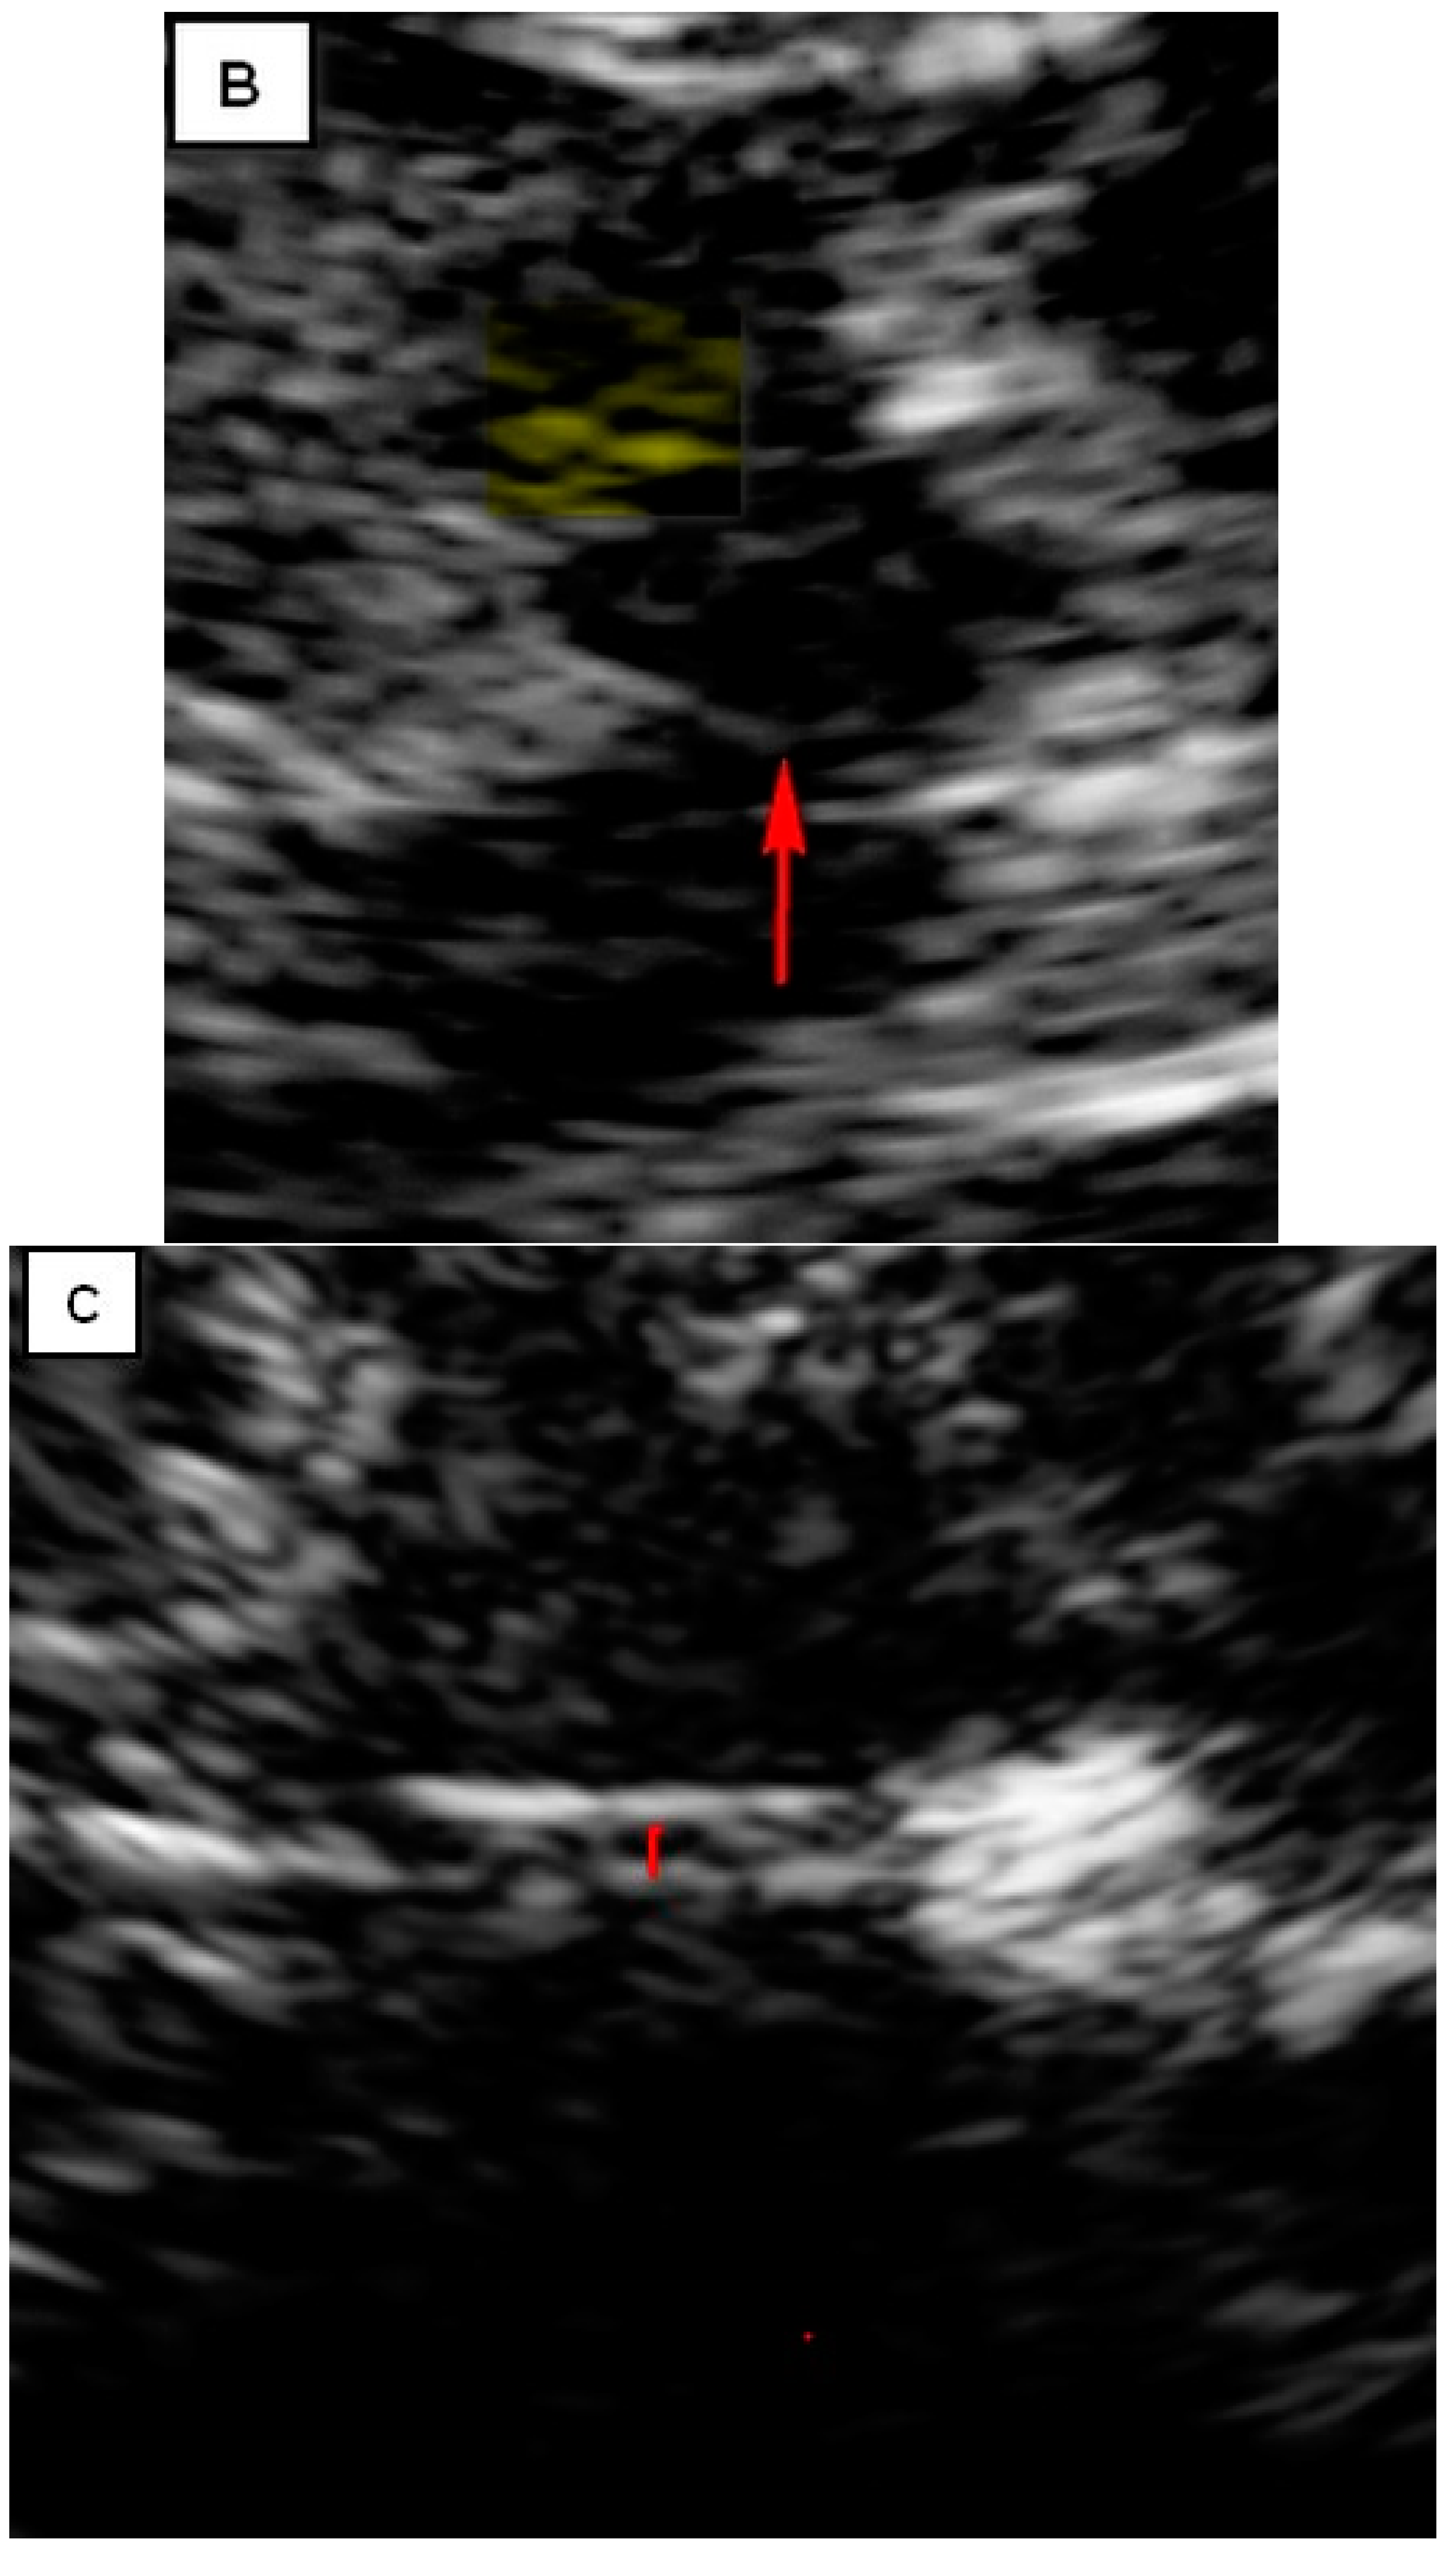

TCS characteristics of interest in our study are illustrated in Table 2. The control subjects consisted of 31 healthy controls, of which there was a slight female predominance (54.8%). The mean age of control subjects was 45.7 ± 11.6 years. The brainstem raphe was discontinued in 33.8% of patients. The SN hyperechogenicity was identified in 79.7% of patients, which represented a significant pathological finding, Figure 1. Third ventricle enlargement (over 6 mm) was present in 79.7% of patients, which can be attributed to gross (whole) brain atrophy, Figure 1. The fourth ventricle was enlarged in 45.9% of patients, which can directly be attributed to the atrophy of the cerebellum and its reduction in volume. The hyperechogenicity of other brain structures, such as the NR, the lentiform nucleus (NL) and the dentate nucleus (ND), is also illustrated in Table 2. We found a statistically significant difference in the hyperechogenicity of SN on the left and the sum quantitively, as well as in the frequencies of hyperintensity between patients with degenerative ataxias and the control subjects (p < 0.05). We have also found statistical significance in the difference between these two groups in the domain of the III and IV ventricles (p < 0.01). Results of mesencephalic atrophy are also presented in Table 2.

Figure 1.

(A) Butterfly-shaped hypoechogenic mesencephalic brainstem insonation level. Normal echogenicity of the brainstem raphe (highly hyperechogenic continuous line, same echogenicity as red nucleus; red arrow); dotted like highly hyperechogenic red nucleus (NR) (yellow arrow); normal echogenicity of substantia nigra (SN) (white arrow). (B) Butterfly-shaped hypoechogenic mesencephalic brainstem insonation level. Hypoechogenic interrupted raphe (red arrow); hyperechogenic substantia nigra (SN) (blurred yellow area, above 0.19 cm2). (C) Third ventricle level insonation depicted as hyperechogenic parallel lines. Normal diameter of the third ventricle (inner borders marked with red line). (D) Third ventricle level insonation depicted as hyperechogenic parallel lines. Dilatated third ventricle (12 mm, inner borders marked with white asterisk).